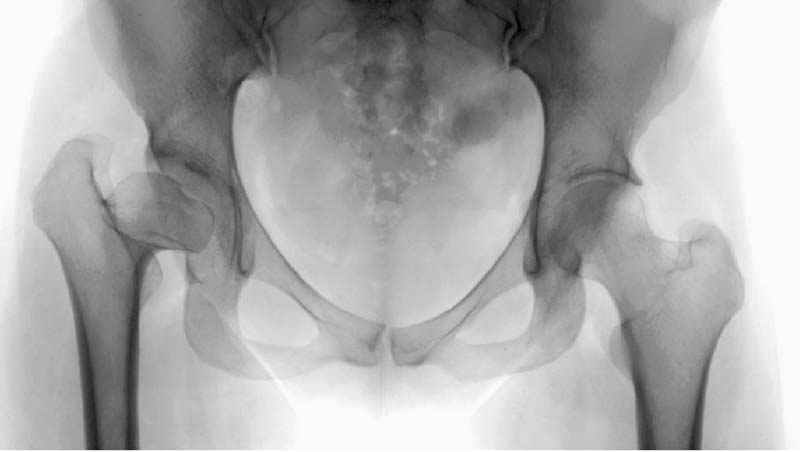

Рис.1 Трехмерная модель тазобедренного сустава с аналогом связки головки бедра. Заметно, что из торца головки выходит капроновый шнур, который с одной стороны прикрепляется к ножке бедренной части модели, а другой его конец, проходя через головку и прикрепляется к вертлужной части модели. Динамометр оказывается не нагруженным, так как аналог связки головки бедра замыкает подвижный узел модели во фронтальной плоскости.

Рис.2 Та же трехмерная модель тазобедренного сустава без аналога связки головки бедра. Пружина динамометра удерживает тазовую часть модели от опрокидывания, поддерживая стабильность так же, как отводящие мышцы обеспечивают ее в отсутствии связки головки бедра.